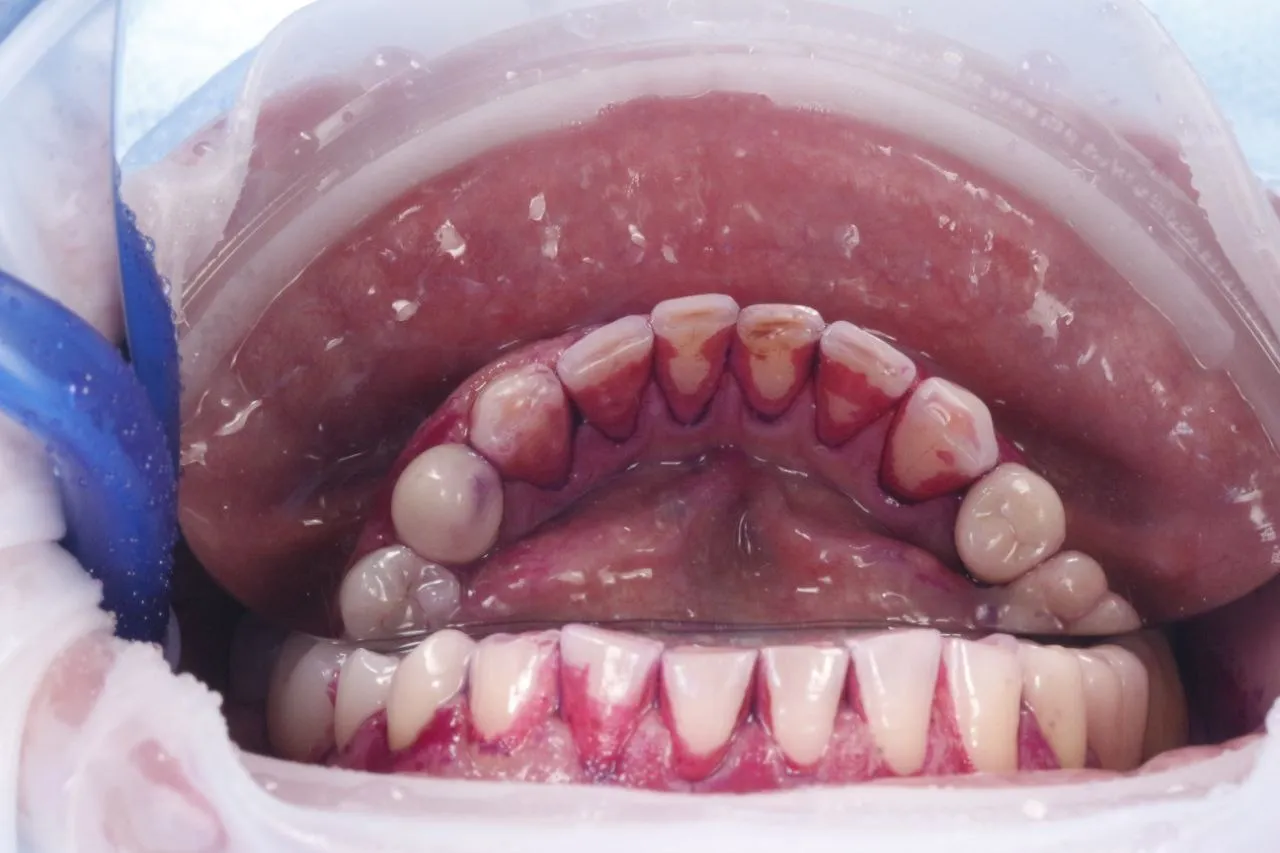

Професійна гігієна порожнини рота